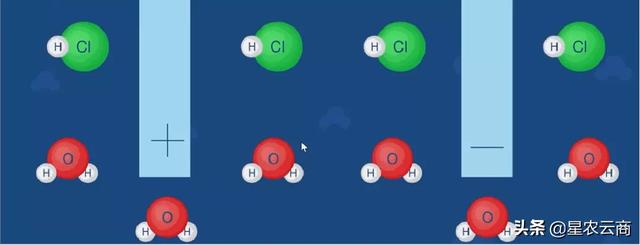

首先,激活的中性粒细胞会发挥吞噬作用吞噬微生物形成吞噬体。在中性粒细胞中存在着大量的颗粒,这些颗粒中含有髓过氧化物酶,形成吞噬体后,中性粒细胞将发生脱颗粒过程,细胞质颗粒的膜与吞噬体融合将髓过氧化物酶排入吞噬体中,形成吞噬溶酶体。同时,存在于中性粒细胞质膜上的NADPH 氧化酶被激活,中性粒细胞发生呼吸爆发,大量消耗氧气产生超氧阴离子( O2-) ,O2-进一步发生歧化反应形成H2O2。髓过氧化物酶催化H2O2、Cl- 形成次氯酸:

H2O2 + 2Cl-→2HClO